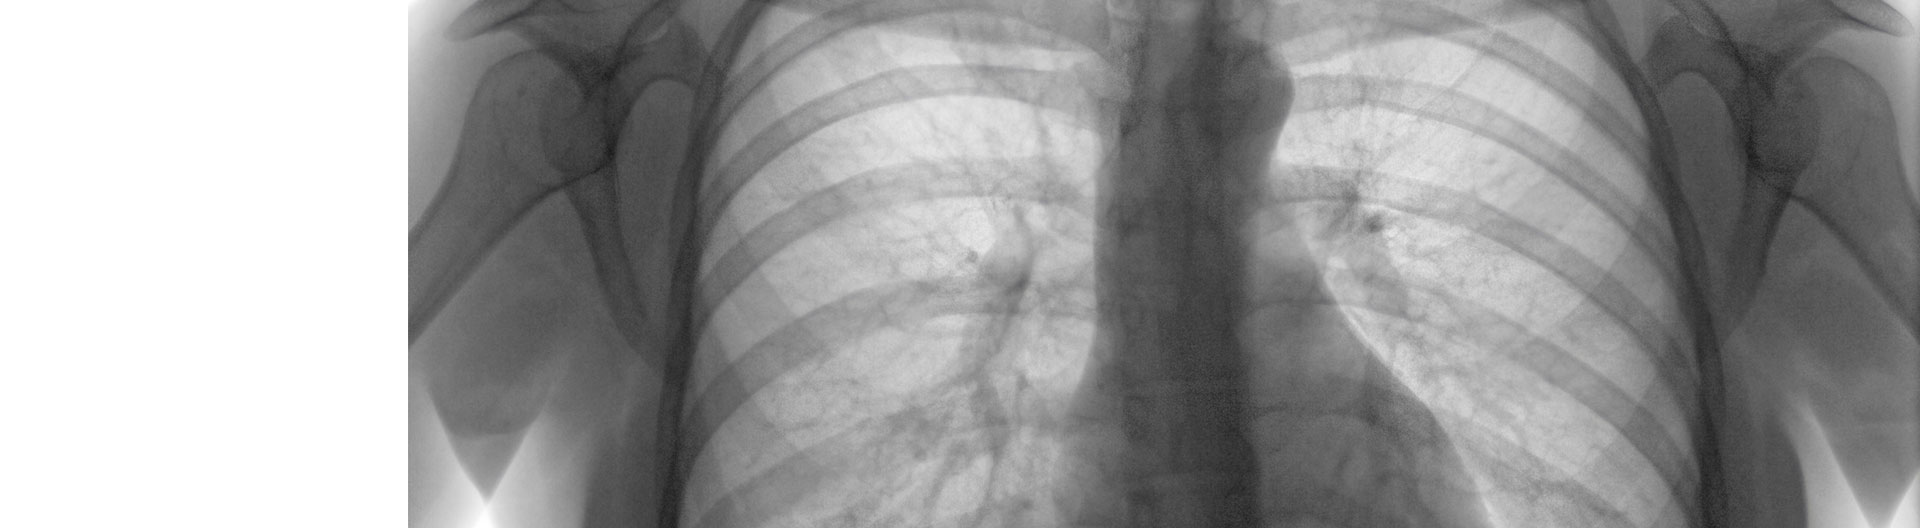

El Curso en Radiología Torácica y Patologías Pulmonares se presenta como una formación especializada diseñada para profesionales del ámbito de la salud que buscan profundizar en el diagnóstico y tratamiento de enfermedades torácicas y pulmonares. En un contexto donde la imagenología juega un papel crucial en la medicina moderna, este programa se enfoca en proporcionar a los participantes las herramientas necesarias para interpretar y aplicar técnicas radiológicas con precisión y eficacia. La relevancia de este curso radica en la creciente demanda de expertos en radiología, especialmente en el ámbito torácico, donde la detección temprana de patologías puede marcar una diferencia significativa en la salud del paciente.

A medida que los participantes avanzan en el curso, la tercera unidad se dedica al fundamento de la imagen radiológica, donde se exploran los principios de formación de imágenes, la atenuación de los rayos X y los criterios de calidad de imagen. Este conocimiento es fundamental para garantizar que las imágenes obtenidas sean diagnósticamente útiles. Posteriormente, en la cuarta unidad, se examinan las principales patologías torácicas, analizando la anatomía y funciones del tórax, así como las lesiones que pueden presentarse en esta área. La tomografía computarizada del tórax se introduce como una herramienta diagnóstica avanzada, ampliando las competencias de los participantes en el uso de tecnologías de imagen modernas.

La quinta unidad se enfoca en la radiología en las principales patologías pulmonares, donde se establecen normas generales para la realización de radiografías de tórax y se describen diversas proyecciones que son esenciales para un diagnóstico preciso. En este contexto, los participantes aprenderán a manejar parámetros técnicos que optimizan la calidad de las imágenes, lo que es crucial para la identificación de condiciones patológicas. La sexta unidad aborda la radiología torácica en el cáncer de pulmón, profundizando en el diagnóstico por imagen y las tecnologías digitales que están revolucionando el campo de la radiología, como la tomografía axial computarizada y la resonancia magnética.

La séptima unidad se centra en la semiología de la radiología de tórax, donde se analizan los factores que influyen en la evaluación de las radiografías torácicas. Este enfoque integral permite a los participantes desarrollar un pensamiento crítico y habilidades analíticas que son esenciales en la práctica clínica. A lo largo del curso, se busca no solo la adquisición de conocimientos teóricos, sino también la aplicación práctica de estos en situaciones reales, lo que potencia la empleabilidad de los graduados en un mercado laboral competitivo.